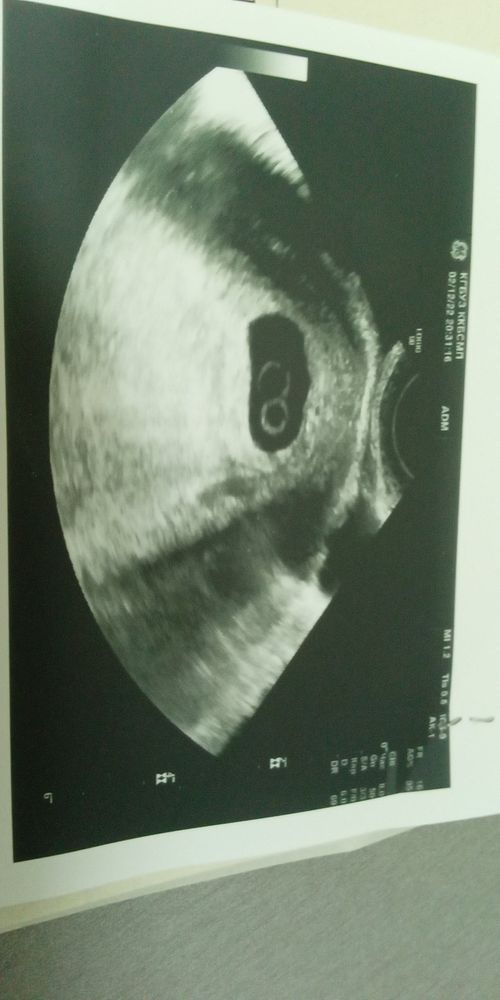

Шок и ничего более 🤦‍♀️😂

Это так двойня выглядит? Здорово 🤩 поздравляю вас! ❤️

Tatiii, спасибо, я в таком шоке на самом деле😂24 числа на узи был ещё один. Сегодня двоя. Надеюсь когда ещё пойду на узи третий не появится😂😂😂

Karina, я думаю что ошибка в первом УЗИ и там не было эмбриона ещё,а сейчас появились и сразу два,так как получается он за неделю не вырос,а даже уменьшился,можно было списать на погрешность,но тогда эмбрион по сути не растет,если эмбрион не растет,то он замирает,то тогда на втором УЗИ сб не было б уже,а сб есть,значит вероятно ошиблись на первом УЗИ Ещё момент у второго очень большой жм,что не есть хорошо (

Поздравляю, это близняшки!) я несколько дней назад тоже в шоке была, надеялась увидеть эмбриона, а увидела двух и 2 сердечка) но у меня двойняшки, а не близнецы)

Врач вам сказал что двойня? Просто в заключении о двойне не нааисано,по узи замерено только 1 ктр, а второго? И про жм только у одного с зачатком эмбриона....или описание не ахти